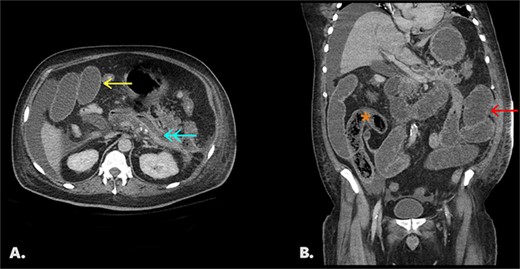

Final CT shows dilated fluid-filled small bowel loops with interval migration of the bezoar into the distal small bowel (Fig. 2).

Follow-up CT with IV contrast (portal venous phase). Fig. 2A: an axial image shows a collapsed pancreatic bed (↞) containing trace fluid, dilated small bowel loops (←), and perihepatic free fluid. Fig. 2B: coronal image of same study shows interval migration of the bezoar into the distal small bowel (*) and upstream dilated, fluid-filled small bowel (←).